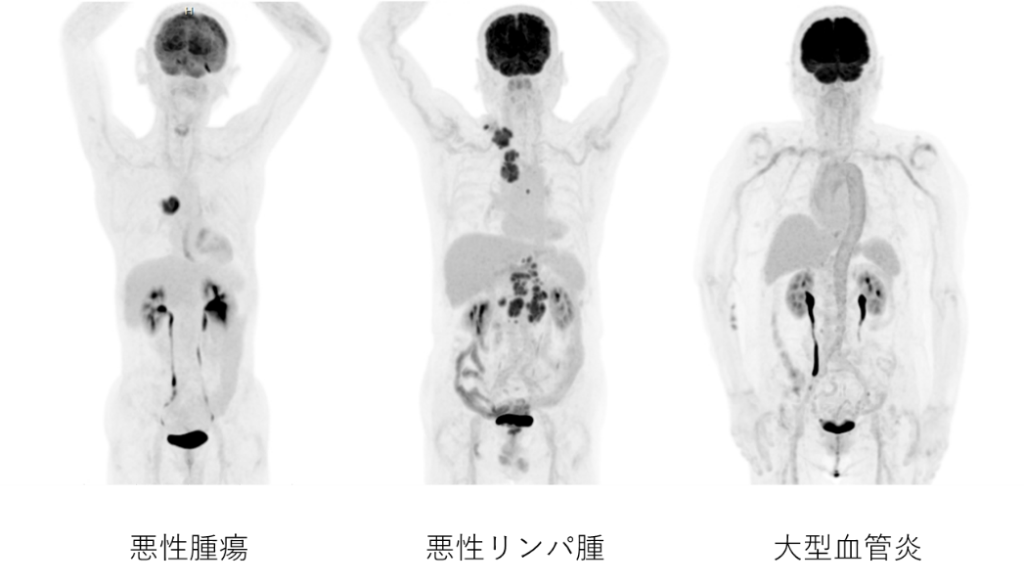

PET検査症例

- 早期胃がんを除く、すべての悪性腫瘍、悪性リンパ腫:他の画像診断により病期診断、転移、再発診断ができない時

- 大型血管炎

特に、肺がん・乳がん・悪性リンパ腫・悪性黒色腫などの腫瘍の検出や転移診断などに有用とされています。